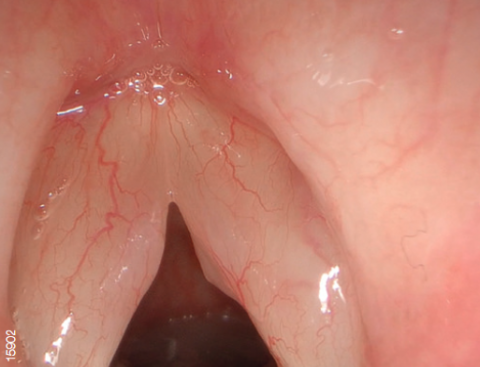

Технология узкоспектральной визуализации изображения NBI

Видеосистема поддерживает режим узкоспектральной визуализации NBI.

NBI - это оптическая технология, которая позволяет визуализировать мельчайшие структуры кровеносных сосудов и слизистой оболочки. В основе технологии лежит принцип поглощения гемоглобином волн определенного спектра (415 и 540 нм). Благодаря уникальным правилам распределения цветов, конечное изображение имеет цветопередачу отличную от обычной.

Свет, попадая в биологическую ткань рассеивается, часть волн (синих и зеленых) поглощается гемоглобином, остальное же распределяется в другие ткани. Поэтому цвет слизистой оболочки желудочно-кишечного тракта в основном определяется гемоглобином. Как упоминалось выше, NBI использует узкополосное освещение с центральной длиной волны 415 и 540 нм. Эти длины волн соответствуют двум пикам поглощения гемоглобина.

Данная технология позволяет с большей точностью визуализировать кровеносные сосуды и слизистую оболочку, а также диагностировать патологические процессы.